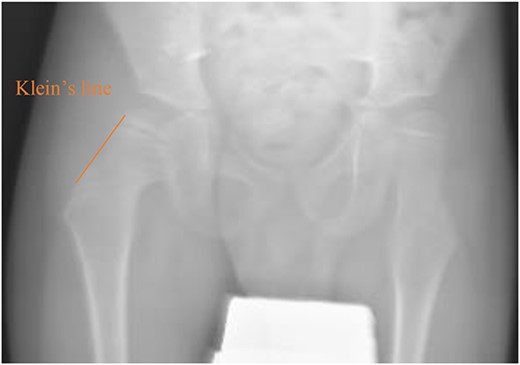

A 5-year-old independent ambulatory Middle Eastern boy with CP who was born preterm and developed grade III intraventricular haemorrhage and periventricular leucomalacia and was on AEDs, including valproic acid (VPA) and levetiracetam (LEV), for >3 years and was controlled over the last year (no history of seizure attack) presented to the emergency room (ER) with right hip pain and inability to bear weight for 4 weeks; the patient had no history of fever or trauma. Physical examination shows a thin, the weight is 12 kg, the height is 101 cm, vital signs within the normal range, tenderness over the right hip, and external rotation of the right hip, with restricted hip mobility. A radiological study was performed ~3 months before the patient presented to the ER for follow-up examination of a left hip coxa valgus deformity with no apparent abnormalities in the right hip (Fig. 1). Initial imaging studies conducted in the ER showed an anterior–posterior view of the pelvic radiograph, revealing Klein’s line [13] not intersecting the capital femoral epiphysis (Fig. 2), and frog-leg lateral view radiograph of the right hip (Fig. 3) confirmed SCFE and Southwick’s slip angle [13] of ~50° (moderate). Laboratory findings were clear for endocrine and renal diseases or infection, except for low vitamin D (total 25-OH Vitamin D: 43.4 nmol/L), suggesting vitamin D insufficiency. The diagnosis was confirmed with clinical and radiological studies as right-sided unstable SCFE requiring surgery. Surgical intervention was performed with percutaneous in situ fixation using a single fully threaded 4.5-mm cannulated screw (Fig. 4). Postsurgical rehabilitation included non-weight-bearing right lower extremities for 6 weeks. Regular follow-up with serial radiology studies showed stable fixation with no migration of screw or further slippage at 6 weeks (Fig. 5) and 3 (Fig. 6), 15 (Fig. 7), and 36 months (Fig. 8). During follow-up, a painless range of motion in the right hip was observed, with full weight-bearing and resumption of his usual activities with no complaints.

Pelvic anterior–posterior radiograph showing coxa valga deformity in the left hip.